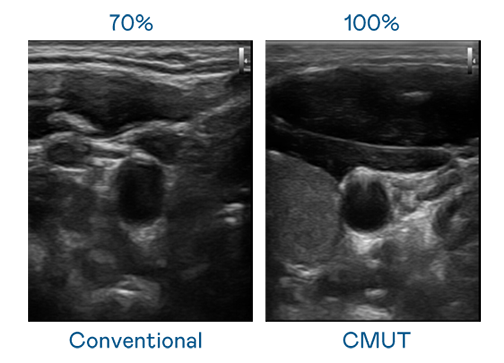

CMUT 技术是一种用电容式微机电元件来产生超音波讯号的技术。与传统 PZT 压电式技术相比,CMUT 频宽增加 30%,更宽频的超音波讯号让影像解析度大幅提升,是实现高影像品质医疗超音波扫描、促进精准医疗发展的关键技术。

大频宽带来超清晰影像

超音波影像的解析度高低,首先取决于探头能发出的讯号频宽。佰富彩 CMUT 可提供高清晰的超音波讯号,提供高频宽、高灵敏度、影像纹理细节更高的超音波影像,协助医护人员缩短影像判读时间及利用精准的医疗影像进行诊断。